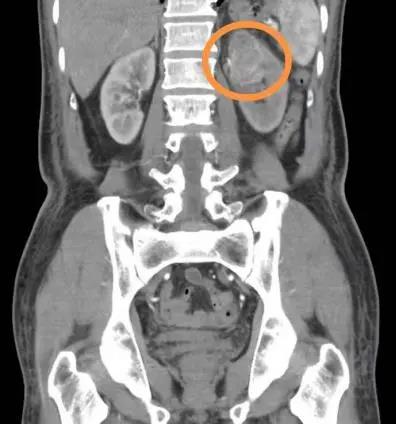

攻堅克難!金年会泌尿外科成功實施後腹腔鏡腎盂癌根治術

近日,金年会泌尿外科獨立完成規範、标準化的後腹腔鏡腎盂癌根治術,标志着我院泌尿外科在腹腔鏡領域又有了一個新的發展及突破。